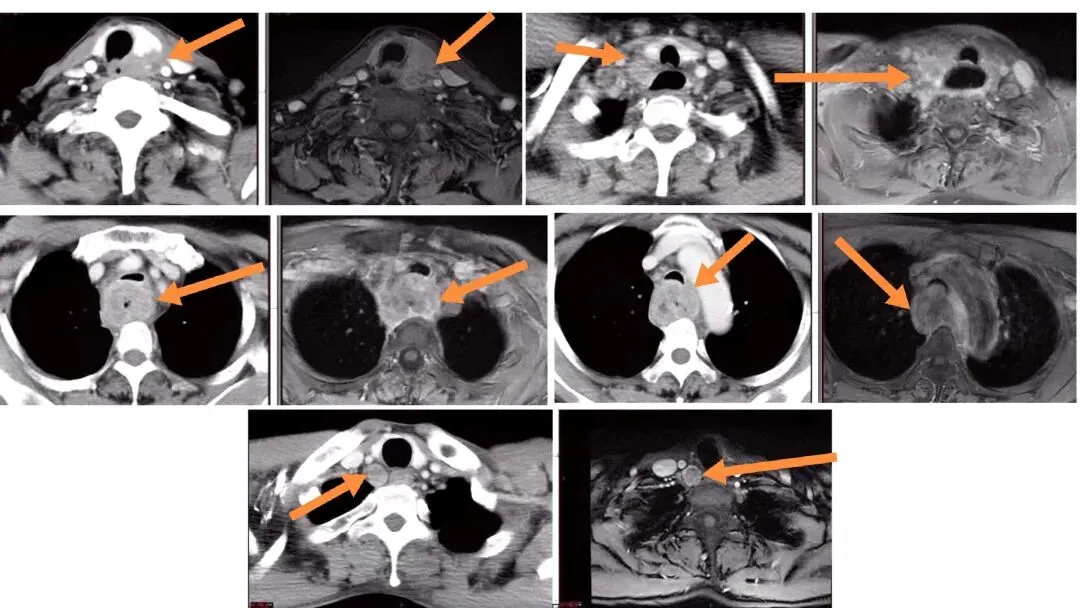

影像学:采用CT+MRI进行双重影像学评估,全面了解肿瘤范围、与周围组织(如喉、下咽、甲状腺)的关系及淋巴结转移情况。

2. 淋巴结评估的重要性:

淋巴结转移极其常见,初诊时总体颈部淋巴结阳性率

转移规律:

上、中颈淋巴结转移率高;

若肿瘤侵犯下咽,则咽后淋巴结转移风险显著增加(下咽后壁癌可达43.5%)。